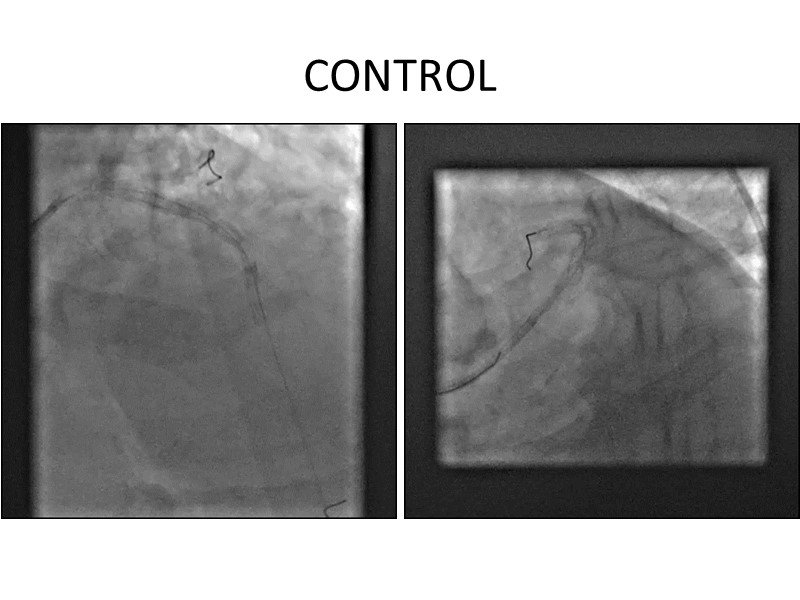

Distal left main stenosis: how to treat optimally with dedicated bifurcation stent BiOSS Lim C. Case-based session